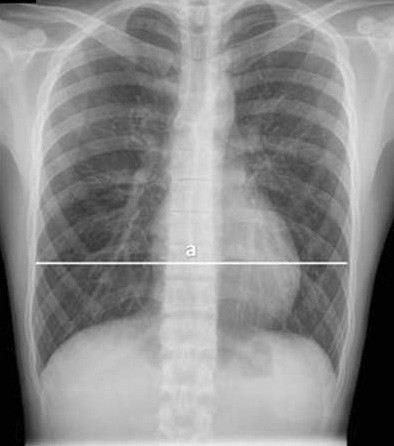

Для точной оценки глубины воронкообразной деформации грудной клетки широко применяется рентгенографическое обследование, которое позволяет визуализировать степень отклонения от нормальной симметрии грудной клетки. Этот метод не только предоставляет необходимую информацию о форме и величине деформации, но и помогает выявить возможные осложнения, такие как нарушения в строении реберных позвонков или хрящей.

Процедура начинается с получения стандартного рентгеновского снимка, на котором четко видны изменения в костных и мягких тканях грудной клетки. Для измерения глубины деформации специалисты используют определенные ориентиры, например, расстояние между передней поверхностью грудной клетки и внутренними органами, а также угол искривления ребер. Это позволяет точно установить степень отклонения и классифицировать его по шкале, принятой в медицинской практике.

• Получение снимков в нескольких проекциях: для точности измерений часто требуется получить рентгеновские снимки в двух проекциях — боковой и прямой. Это позволяет лучше оценить трехмерное изменение формы грудной клетки.

• Оценка симметрии грудной клетки: на снимках специалист обращает внимание на степень асимметрии, так как это может существенно влиять на выбор метода лечения или операции.